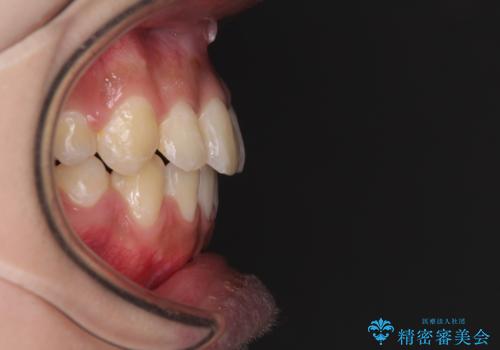

- 八重歯と上下前歯のでこぼこを気にして来院された患者様です。

上下前歯部叢生のスペース獲得のため、上下顎左右小臼歯各1歯(計4本)と全ての親知らずを抜歯して、矯正治療を行うこととしました。

上下の正中位置が大きくずれていたため、治療期間の長期化や正中が合わないまま終了することが予想されましたが、思っていた以上にスムーズに歯が移動し、満足いただける仕上がりとなりました。